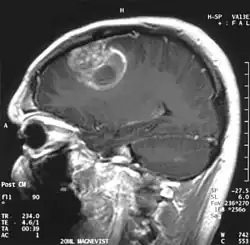

![]() | |

| A coronal view (from the back of the head) of a contrast-enhanced MRI revealing a glioblastoma in a 15-year-old boy | |